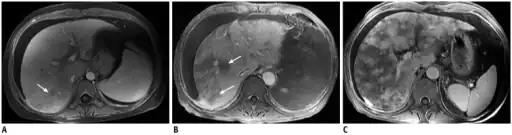

Post contrast-enhanced MR images show severity of patchy liver enhancement in hepatic sinusoidal obstruction syndrome.A. Grade 1. Arrow denotes mild patchy enhancement. B. Grade 2. Arrows denote moderate confluent patchy enhancement. C. Grade 3. Severe case with diffuse confluent patchy enhancement. Note all three cases demonstrate ascites.

Post contrast-enhanced MR images show severity of patchy liver enhancement in hepatic sinusoidal obstruction syndrome.A. Grade 1. Arrow denotes mild patchy enhancement. B. Grade 2. Arrows denote moderate confluent patchy enhancement. C. Grade 3. Severe case with diffuse confluent patchy enhancement. Note all three cases demonstrate ascites.